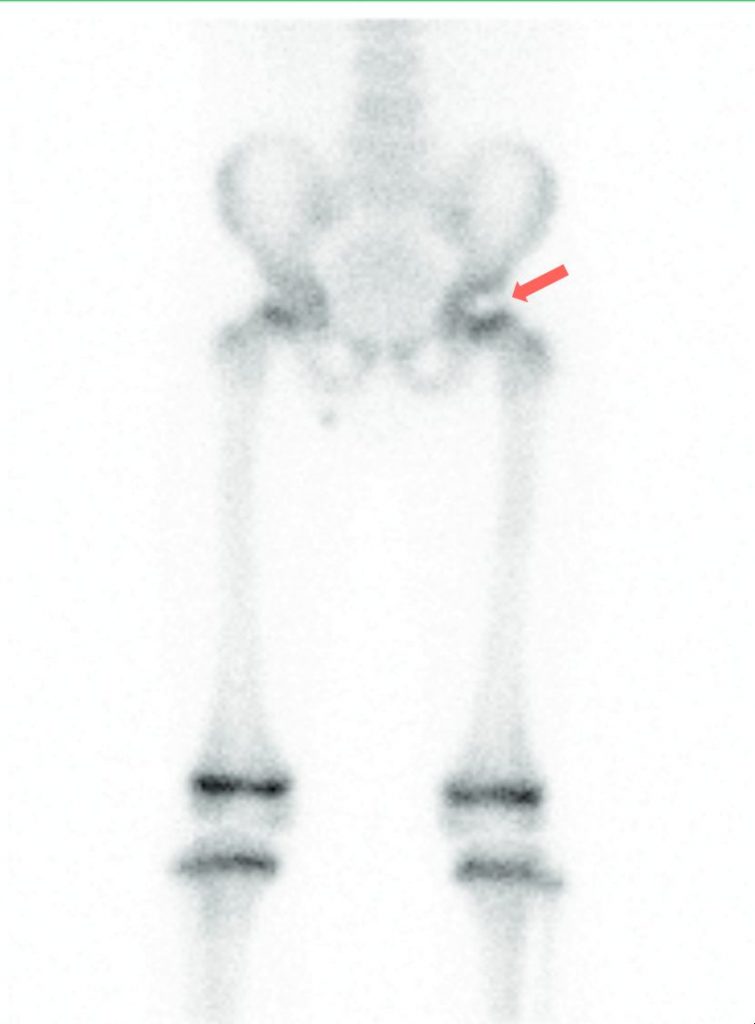

Ces signes s’accompagnent de remaniements de la métaphyse. Puis la tête va se revasculariser (aspect fragmenté de l’épiphyse). Enfin, cette dernière va se remodeler à un stade tardif. L’échographie, si elle est faite, met en évidence un épanchement intra-articulaire de façon inconstante. La scintigraphie montre une hypofixation du noyau épiphysaire de la tête fémorale (figure 114.3).

Fig. 114.3 Scintigraphie osseuse en face antérieure montrant une hypofixation du noyau épiphysaire de la tête fémorale gauche (flèche rouge) en lien avec une ostéochondrite.

Source : CERF, CNEBMN, 2022.